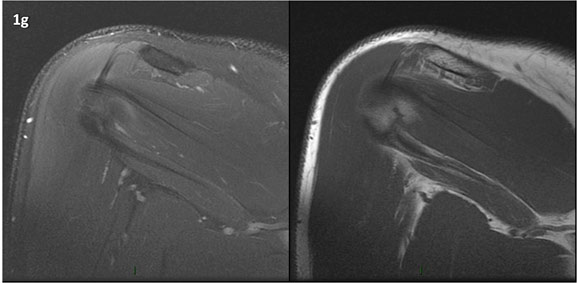

Figura 1 (a-g): Imagens consecutivas de RM no plano coronal nas ponderações DP com supressão de gordura (DP SG) à esquerda e T1 à direita. Clique na seta para passar as imagens.

Figura 1 (a-g)': Imagens consecutivas de RM no plano coronal nas ponderações DP com supressão de gordura (DP SG) à esquerda e T1 à direita mostrando . Clique na seta para passar as imagens.

Figuras 1b’ a 1g’ mostrando atrofia da porção superior do músculo redondo menor (seta salmão), com lipossubstituição mais evidente das mais fibras laterais (seta amarela). As fibras mais inferiores e mediais têm atrofia menos evidente.

Repare que estas alterações não são evidentes nas imagens com supressão de gordura.